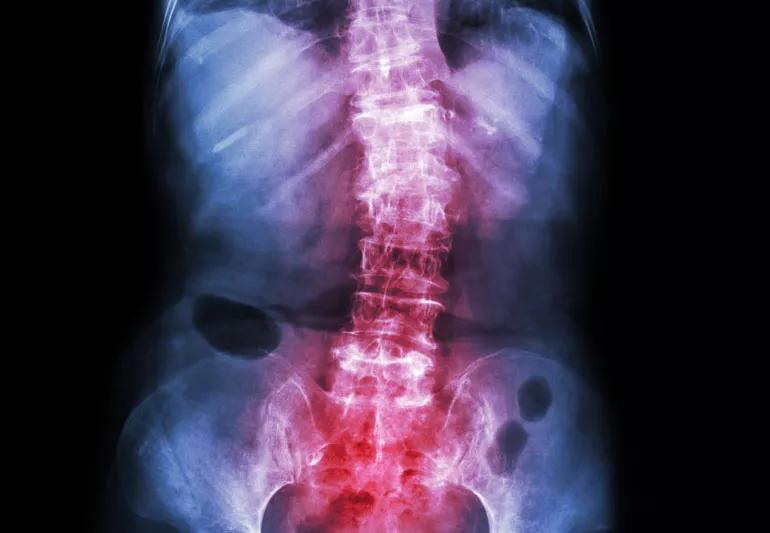

Adult X-ray showing scoliosis

You may have more power over adult scoliosis than you think. Doctors can offer you various treatment options, and there are things you can do to help yourself. Here are five things you might be surprised to hear about adult scoliosis.